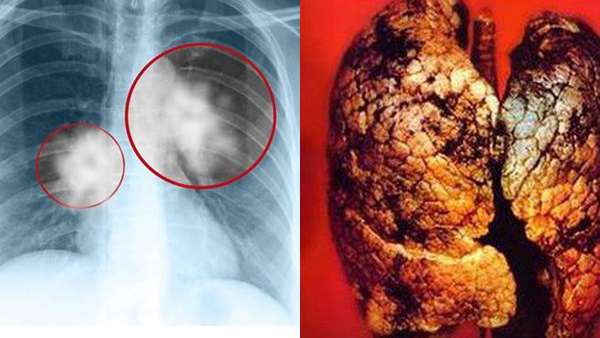

Trẻ nhất Việt Nam, nam sinh 17 tuổi chết vì ung thư phổi

Mắc ung thư phổi từ khi mới 15 tuổi, dù được điều trị nhiều biện pháp tích cực nhưng bệnh nhân đã tử vong 2 năm sau đó.